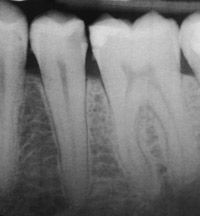

The patient presents with a mandibular premolar with a large distal carious lesion (Figs. 1 and 2).

Fig. 1